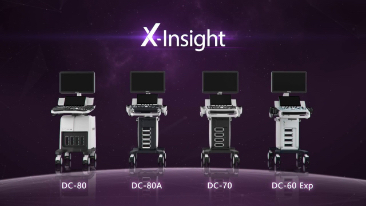

X-Insight is een inzichtelijke oplossing om meer visie te krijgen.

De gloednieuwe oplossing van Mindray is het geslaagde product dat is voortgekomen uit voortdurende klantinzichten in klinische behoeften in combinatie met steeds evoluerende, geavanceerde ultrasoundtechnologie?n. Vol energie en gebrand op toekomstgerichte inzichten en eindeloze mogelijkheden: dankzij de verhoogde schaalbaarheid wordt de oplossing continu verbeterd.

Als allround partner zet DC-60 Exp met X-Insight zich in om een allesomvattende oplossing te zoeken waarmee u alle aspecten van uw dagelijkse klinische activiteiten gemakkelijk en trefzeker kunt beheren.

De DC-60 Exp met X-Insight is ontworpen op basis van diepgaand inzicht in klantbehoeften om hoge effici?ntie met nauwkeurige beeldverwerking te leveren, dankzij eXacte helderheid, eXceptionele intelligentie en eXcellente ervaring.